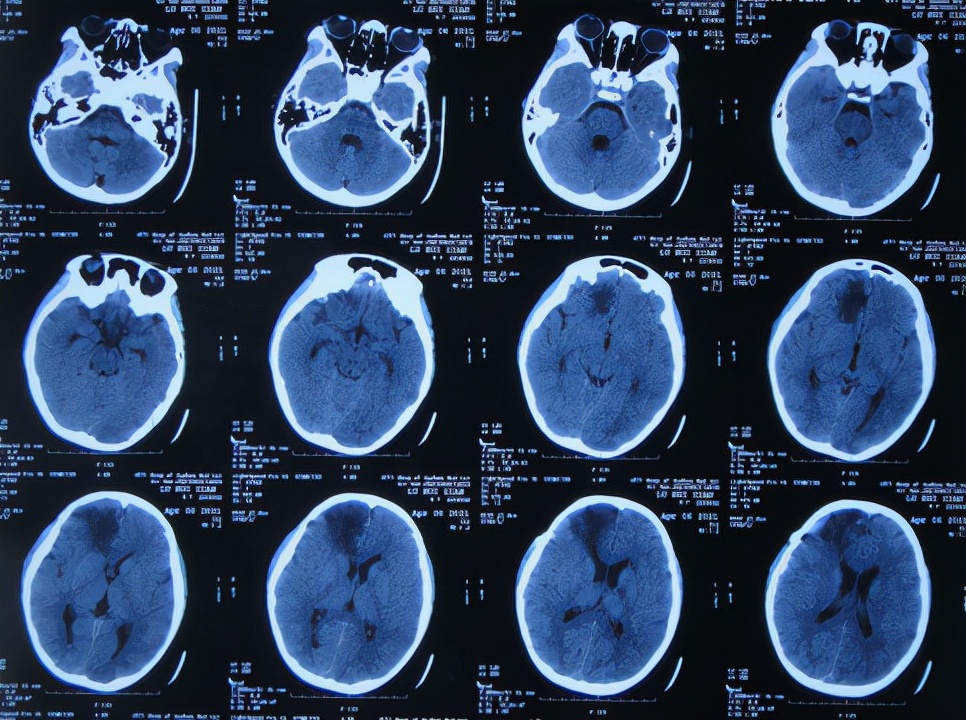

次日即2021年3月24日,转入该院的神经外科,仍发热体温高达38.0-39.0℃,查脑CT示出现水肿,仍有出血( 图-3 ),给予抗感染治疗。

图-3: 2021年3月24日脑CT